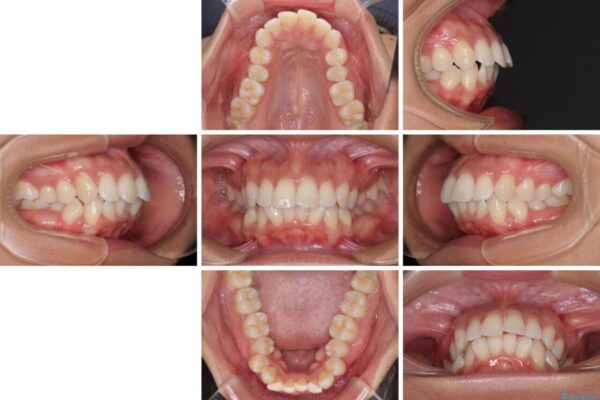

下唇が突き出るような口元の突出感が気になるとのことで来院された患者様です。

上下顎ともに前突した歯列であったので、上下ともに左右の第1小臼歯4本を抜歯し、ワイヤー装置にて矯正治療を行うこととしました。

抜歯スペースに前歯を移動させることで歯の突出感が改善され、非常に唇が閉じやすい仕上がりとなりました。

治療後